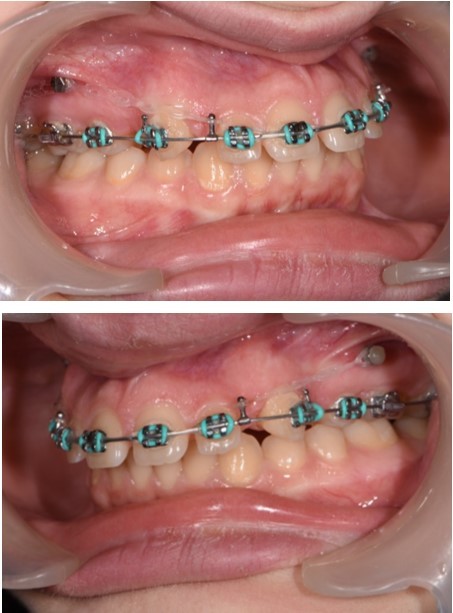

In order to emphasize one of the major indications of skeletal anchorage with mini implants, a clinical case was selected. A young teenage patient (Figure 1, Figure 2, Figure 3, Figure 4), with a severe overjet, flared upper incisors with spacingand a convex profile was reffered to our dental office. Treatment objectives were established from the beggining: retrusion of the upper anterior teeth, overjet and overbite correction, space closure and obtaining a better occlusion. Anchorage needs were evaluated. Absolute anchorage was needed in order to obtain upper dental retrusion without mesial movement of the posterior teeth. Two mini implants were placed bilaterally, in a labial position, between the second premolars and upper first molars. Both mini plates and mini implants provide a predictable result in this case but since mini implants are more easy to place and provide a higher degree of comfort, this option seemed more suitable. In this way, the need for other anchorage devices, such as a palatal arch or headgear was eliminated. The upper incisors and canines can be now distalized and intruded, after the upper premolar extraction.

Treatment started with orthodontic appliances on the upper arch, Roth 022" prescription. In order to achieve a better retraction of the upper teeth, first bicuspids were extracted. Retraction of the upper incisors with elastics chains placed from crimpable hooks to orthodontic implants.

The working stage of the treatment was done with the use of a rectangular stainless steel archwire 0.019”x0.025” (Figure 5, Figure 6). Bodily movement was obtained and a minor intrusion. The incisal edges were displaced backward in order to provide a better incisal display at rest and during the smile. Unlike palatal arches, where the retraction is done by tipping the incisors, the mini implants in our case were able to provide a bodily retraction of the upper anterior teeth. Therefore, retraction was obtained with no anchorage loss. The improvement in the overjet and overbite was good.

Figure 5.Retraction of the upper incisors with elastics chains placed from crimpable hooks to orthodontic implants.

Figure 6.Significant overjet and overbite improvement after implant based orthodontic retraction.